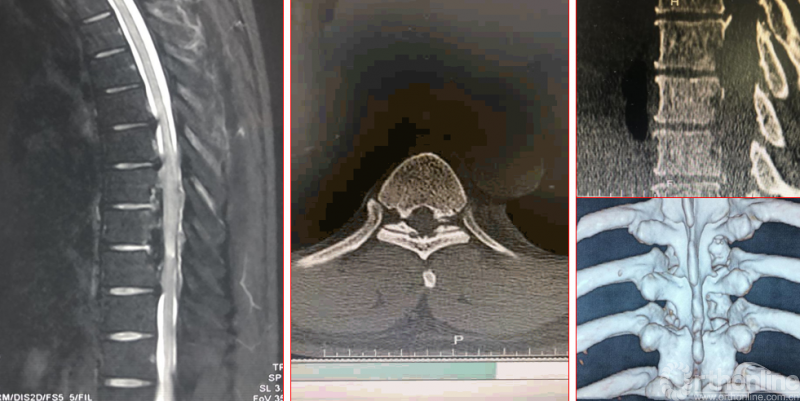

术前诊断及评分

JOA评分:5分

ASIA等级:C级

诊断:

1:胸椎间盘突出伴钙化下肢不全瘫

术前资料

术后影像学资料

术后病情评估

术后第二天

JOA评分:8分;RR:37.5%(可);ASIA等级:D级。

术后8个月资料